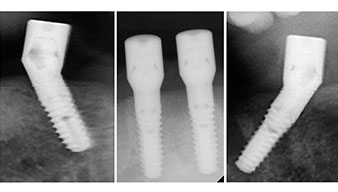

A three-dimensional cone beam computed tomography scan (CBCT, Planmeca) was performed to aid planning and minimize risks. This revealed that the quality and quantity of the available bone were sufficient for the surgery and immediate restoration using the Fast & Fixed method. Following the protocol for this concept, the implants are inserted at 35, 32, 42 and 45. Angling the distal implants by up to 45° shifts the emergence profile to posterior and generates a larger support polygon (Fig. 3).

This corresponds to the next preset position in the Implantmed. Here we see the W&H contra-angle handpiece being held at a 45° angle to mesiocaudal in the region of 45 in order to preserve the mental nerve. The mental foramen is used as the anatomic reference for all drilling in this region. The subsequent holes were drilled at a reduced speed of 300 rpm (Fig. 10 and 11).

Angled abutments (35°) were screwed in to compensate for the divergence of the distal implants, with the result that the emergence profile of all implants was as perpendicular as possible to the bite plane. This is a prerequisite for occlusal placement of the provisional and subsequently the permanent denture (Fig. 15 and 16).

The light increases the contrast in the oral cavity and improves visual perception. Both the contra-angle handpiece and the S-11 straight handpiece from W&H are externally cooled, which can be seen as a great advantage because the saline solution arrives exactly where it’s needed and can also be subsequently adjusted if necessary. The contra-angle and straight handpieces can be dismantled, which is highly recommended for hygiene and sterilizability. Four SKY implants measuring 4.0 x 14mm were placed.